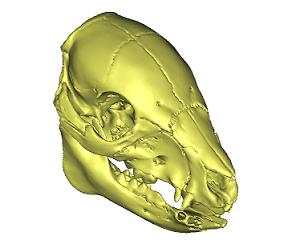

In 2007, the OBL began investigating the biomechanics of skull fracture in children and infants. By researching the material and mechanical properties of the developing porcine skull, our researchers can gain an accurate perspective of the developing human skull. The OBL will be working with Anthropologists at MSU to develop an in-depth tool to predict pediatric skull fracture patterns.